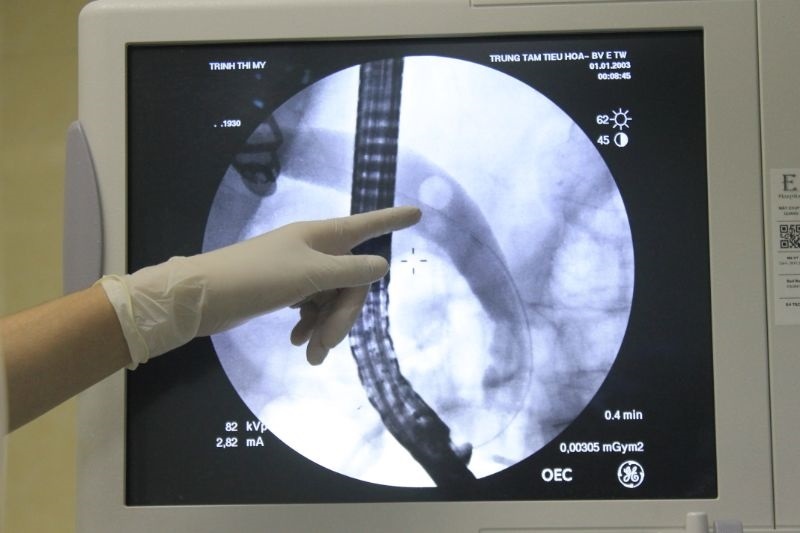

Viên sỏi kích thước lớn khoảng 10 mm nằm trong túi mật của bệnh nhân. Ảnh: BVCC.

Do vậy, các bác sĩ Bệnh viện E quyết định sử dụng phương pháp nội soi mật tụy ngược dòng (ERCP) cấp cứu để can thiệp lấy sỏi ống mật chủ. Trong khi nội soi, bác sĩ phát hiện viên sỏi nằm trong ống mật chủ có đường kính tương đối lớn, khoảng 10 mm, làm giãn to ống mật chủ.